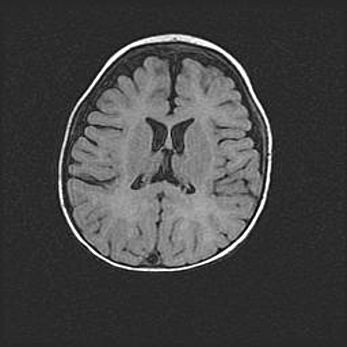

Наружная гидроцефалия с возможной атрофией височных областей.

Возраст: 28 дней

Вес: 3670 г

Пол: мужской

Окружность головы: 38 см

Срок гестации: 40 недель

Гидроцефалия головного мозга у новорожденных – это заболевание, которое характеризуется скоплением избыточного количества спинномозговой жидкости в желудочковой системе головного мозга в результате затруднения её перемещения от места выработки к месту поглощения в кровеносную систему или вследствие нарушения абсорбции. При открытой наружной форме гидроцефалии у новорожденных расширяются и переполняются субарахноидные пространства.

При нормотензивных  формах,  которые,  как  правило,  являются  следствием  перенесенных ишемических  повреждений  паренхимы  мозга,  возможно  сочетание микроцефалии  с нормотензивной гидроцефалией. В основе данных изменений лежит атрофия больших полушарий с преимущественной  локализацией  в  лобно-височных  областях.